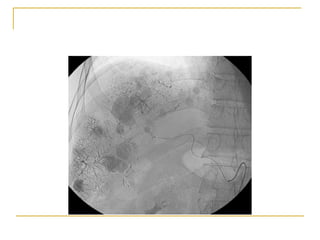

TARE

Yttrium 90 is a β particle emitter as it decays to stable zirconium-90

Maximum penetration < 10mm (mean < 2.5 mm)

Half life of 64 hrs, mean life of 3.85 days

94% of radiation delivered in 11 days

Tumor to non-tumor uptake may triple the absorbed dose in tumor

Response

Imaging more difficult to interpret

Less embolization effect so enhancement not eliminated

Looking for changes in lesion size

Treatment response slow (6m)

Changes in liver morphology common